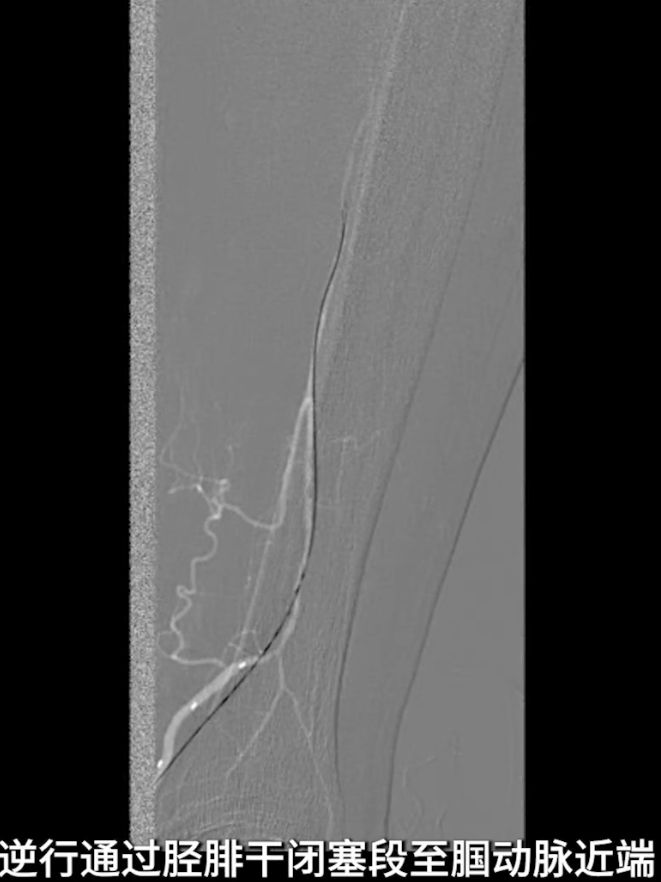

逆穿技术应用:改为逆穿胫后动脉远端,支撑导管配合V18导丝经交通支逆行进入腓动脉远端,逐步推送导丝导管通过胫腓干闭塞段,直至腘动脉近端真腔,与近端导管完成对接,建立膝下流出道操作轨道。

流出道扩张与优化:使用3.0×200mm PTA球囊对“胫腓干-腓动脉”全程进行扩张;